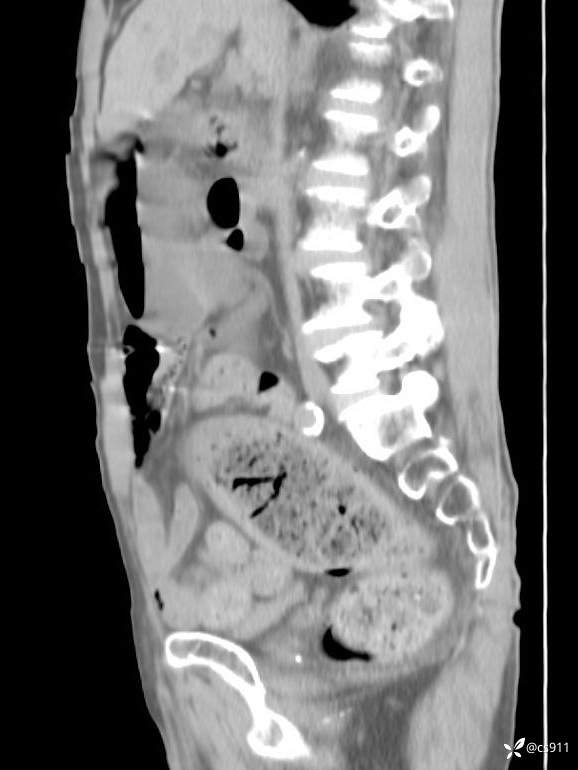

急腹症之急诊CT,原因?答案公布

男,77岁,腹痛、腹胀伴恶心呕吐1天。呕吐胃内容物,非喷射性呕吐,有咖啡色样胃内容物,诉有胃穿孔病史。查体:全腹平,下腹部压痛,全腹无反跳痛,叩诊呈浊音,移动性浊音阴性,肠鸣音减弱,1-2次/分。肛检:直肠未扪及明显肿物,可触及大量粪块。

血淀粉酶(AMY) HH 1859 U/L 35-135

癌胚抗原(CEA) H 27.44 ng/ml 0-5